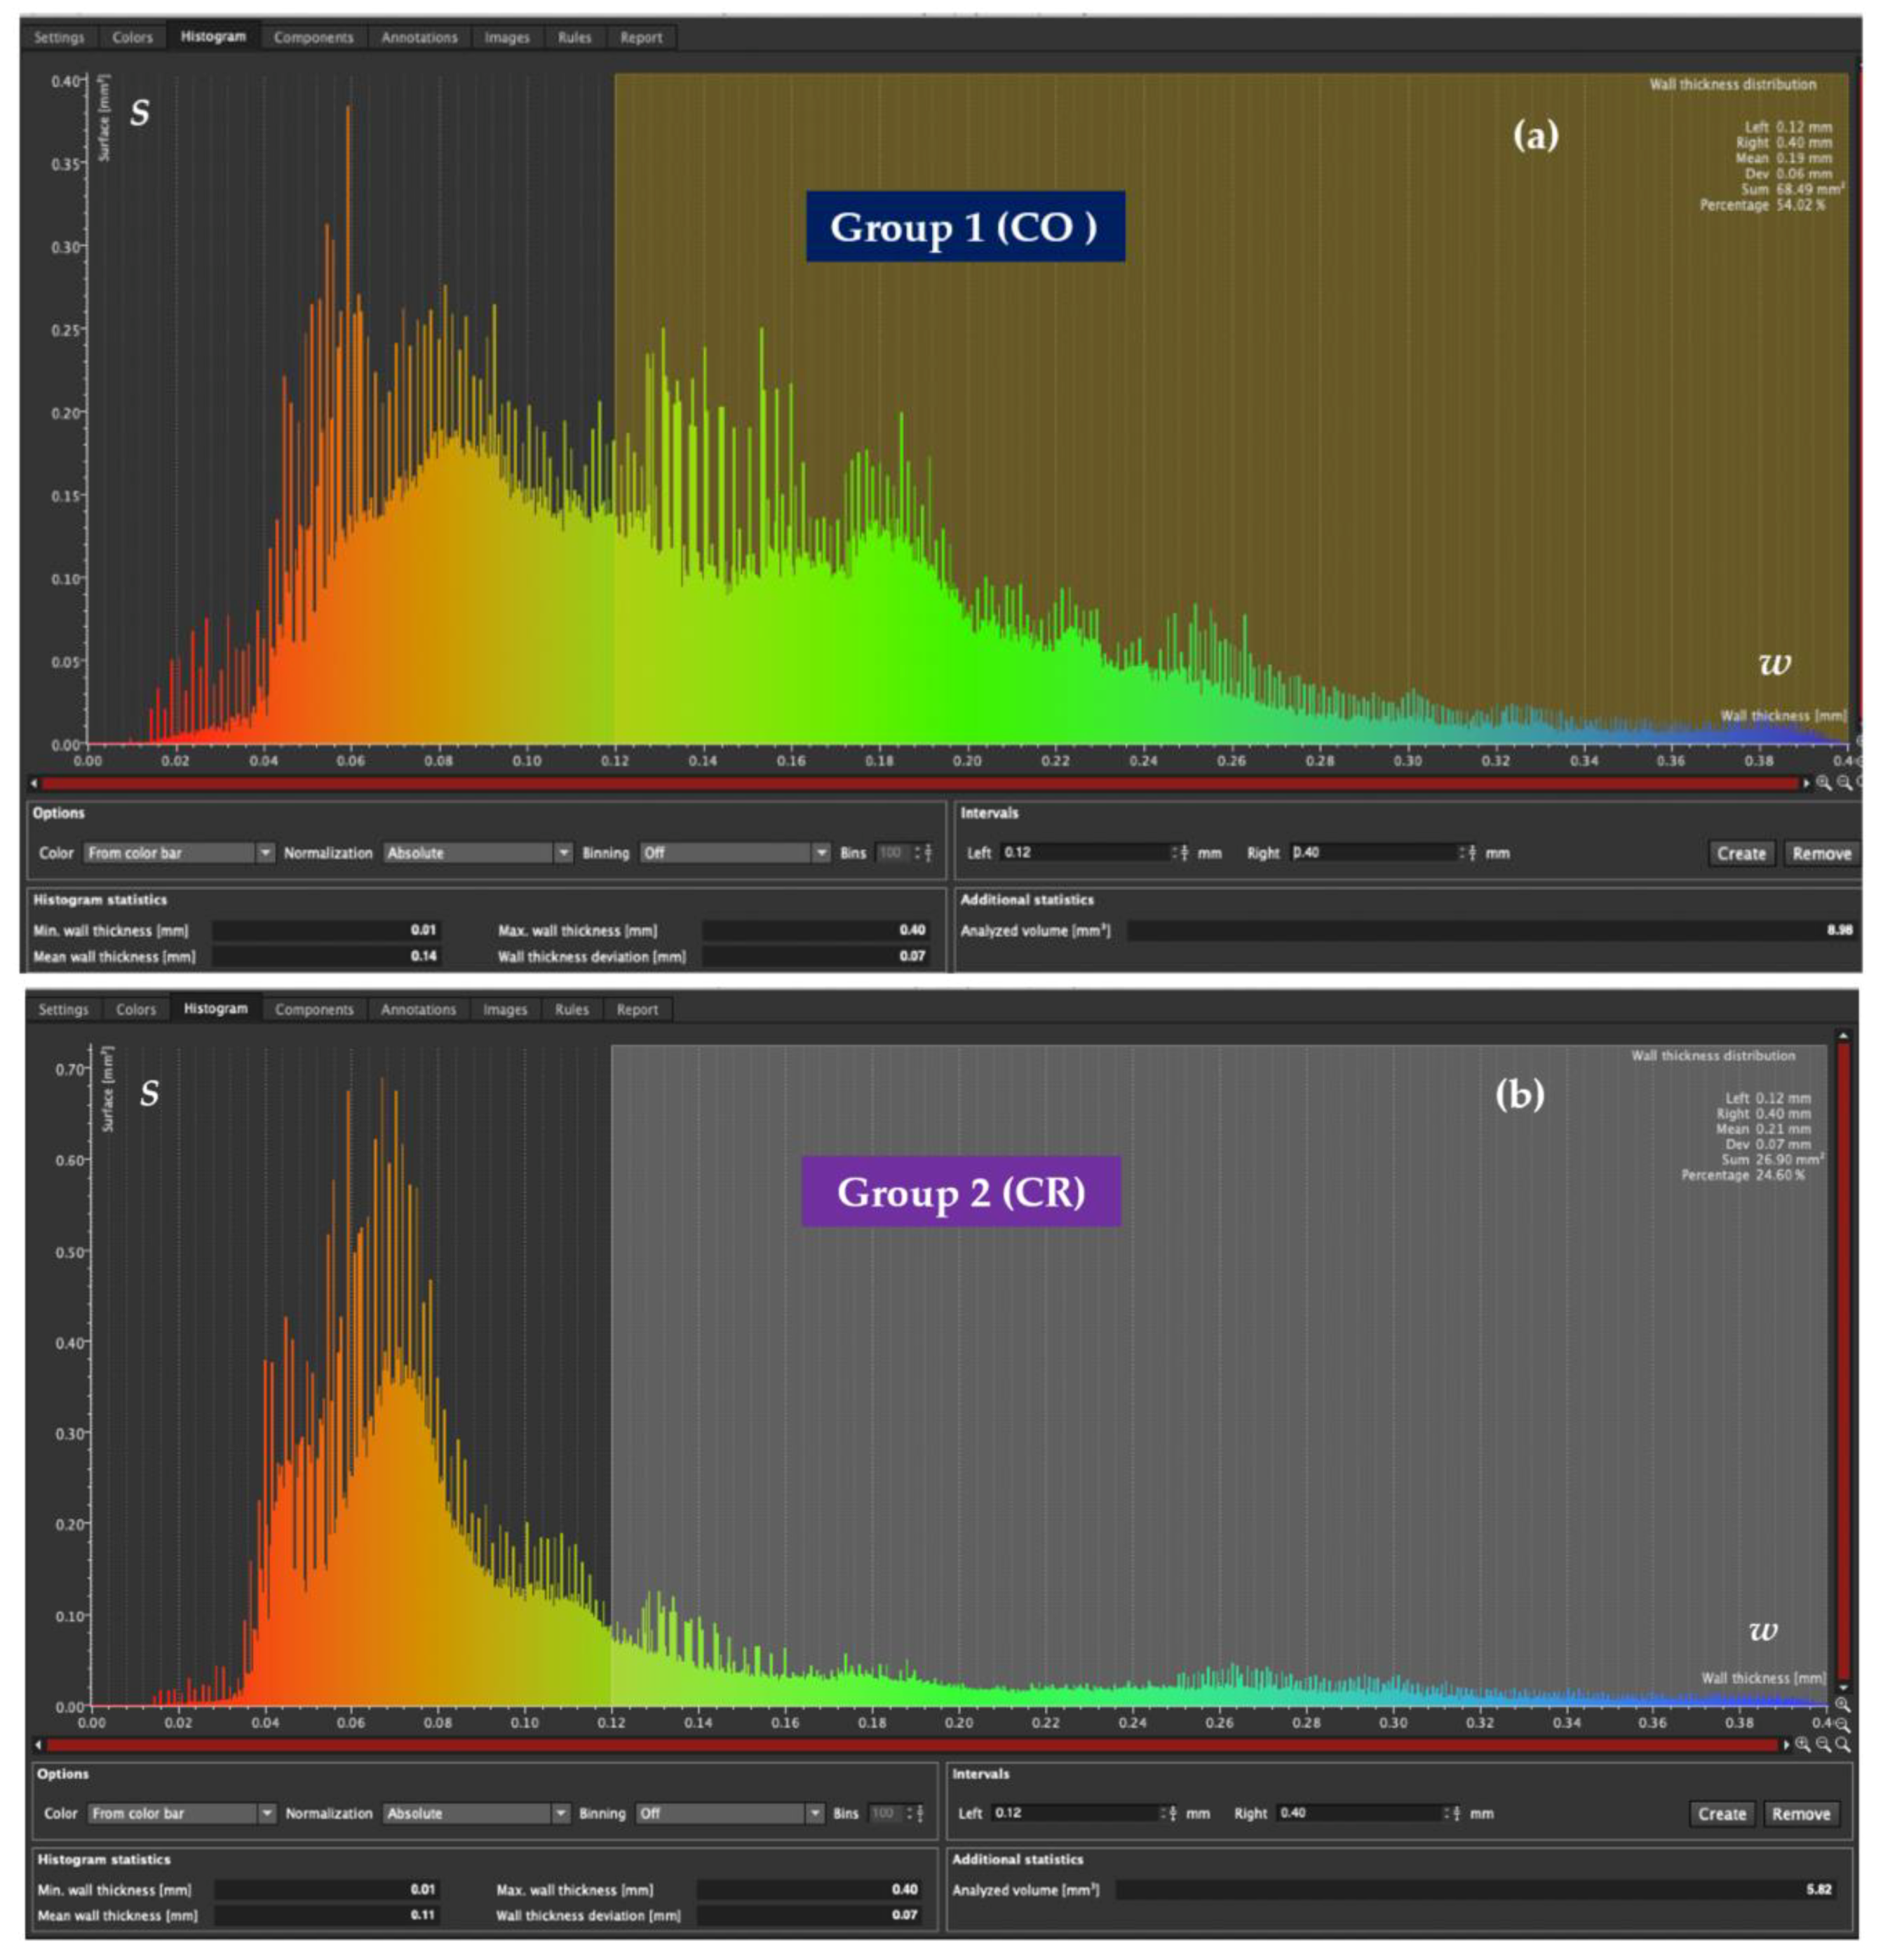

3.3. Mathematical Modeling of the Micro-CT Results

3.4. Porosity Results

| Intervals of Cement width w (μm) | Average Covered Surface S (%) | |

|---|---|---|

| Group 1, CO Veneers | Group 2, CR Veneers | |

| 0–120 | 64.55 | 81.56 |

| 120–400 | 35.45 | 18.31 |

| Group | N | Mean ± Standard Deviation (%) | Standard Error Mean (%) | Mean Rank | Sum of Ranks | p |

|---|---|---|---|---|---|---|

| (1) CO veneers | 12 | 64.56 ± 9.728 | 2.808 | 6.92 | 83.00 | <0.001 s |

| (2) CR veneers | 12 | 81.57 ± 4.619 | 1.333 | 18.08 | 217.00 |